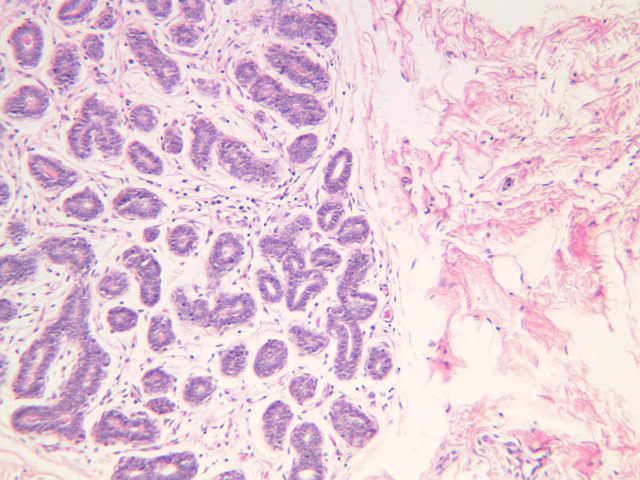

Secretory Phase

This phase occurs on days 15 to 27 and corresponds to the ovarian luteal phase characterized by rising levels of progesterone. The epithelial cells begin to secrete a mucoid fluid rich in nutrients, especially glycogen. The glands become highly coiled and folded and toward the end, very distended. The density of the stroma lessens as it becomes edematous. (slides B-99 [2.5x, 10x, 20x, 40x] [2.5x, 10x, 20x, 40x]; B-100 [1x, 2.5x] [2.5x, 10x, 20x, 40x] [2.5x, 10x, 20x, 40x])